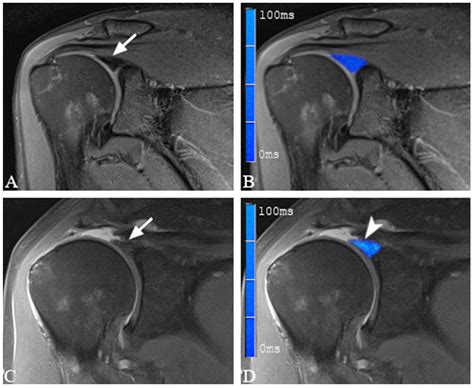

• Imaging Tests: Magnetic Resonance Imaging (MRI) is the gold standard for diagnosing Slap Tear Types. An MRI arthrogram, which involves injecting contrast dye into the shoulder joint, can provide more detailed images of the labrum and surrounding structures.